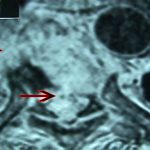

Εικ. 4: Μαγνητική τομογραφία της Θ.Μ.Σ.Σ. εγκάρσια λήψη, ακολουθία Τ1 & Τ2

Διαπιστώνεται η καταστροφή του μεσοσπονδυλίου δίσκου, φλεγμονώδεις περισπονδυλικές μάζες πλαγίως και προσθίως και οπισθίως ύπαρξη επισκληριδίου αποστήματος